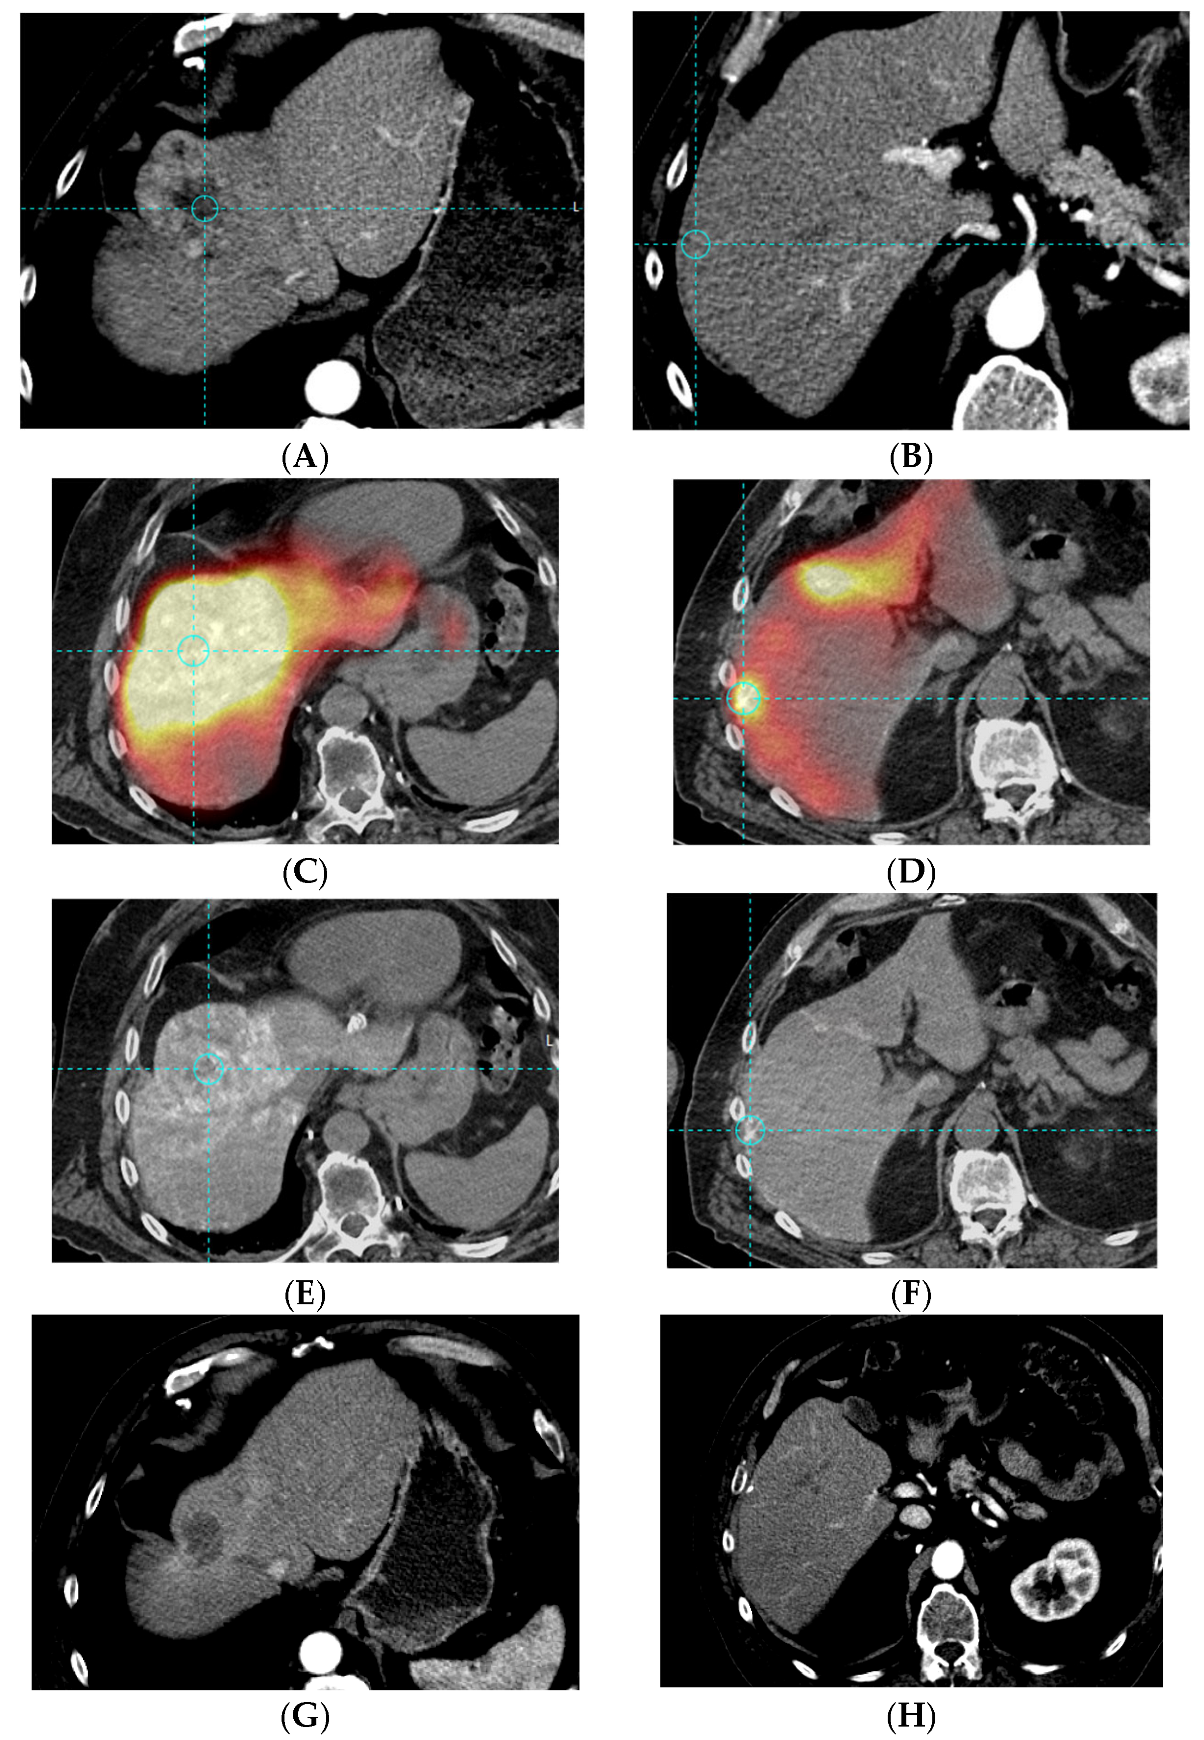

2.4. Bio-Distribution Assessment

2.4.1. Image Acquisition

2.4.2. Quantitative Analysis

2.4.5. Tumor Response Assessment

3.2. Bio-Distribution

3.3. Dosimetry

3.4. Tumor Response